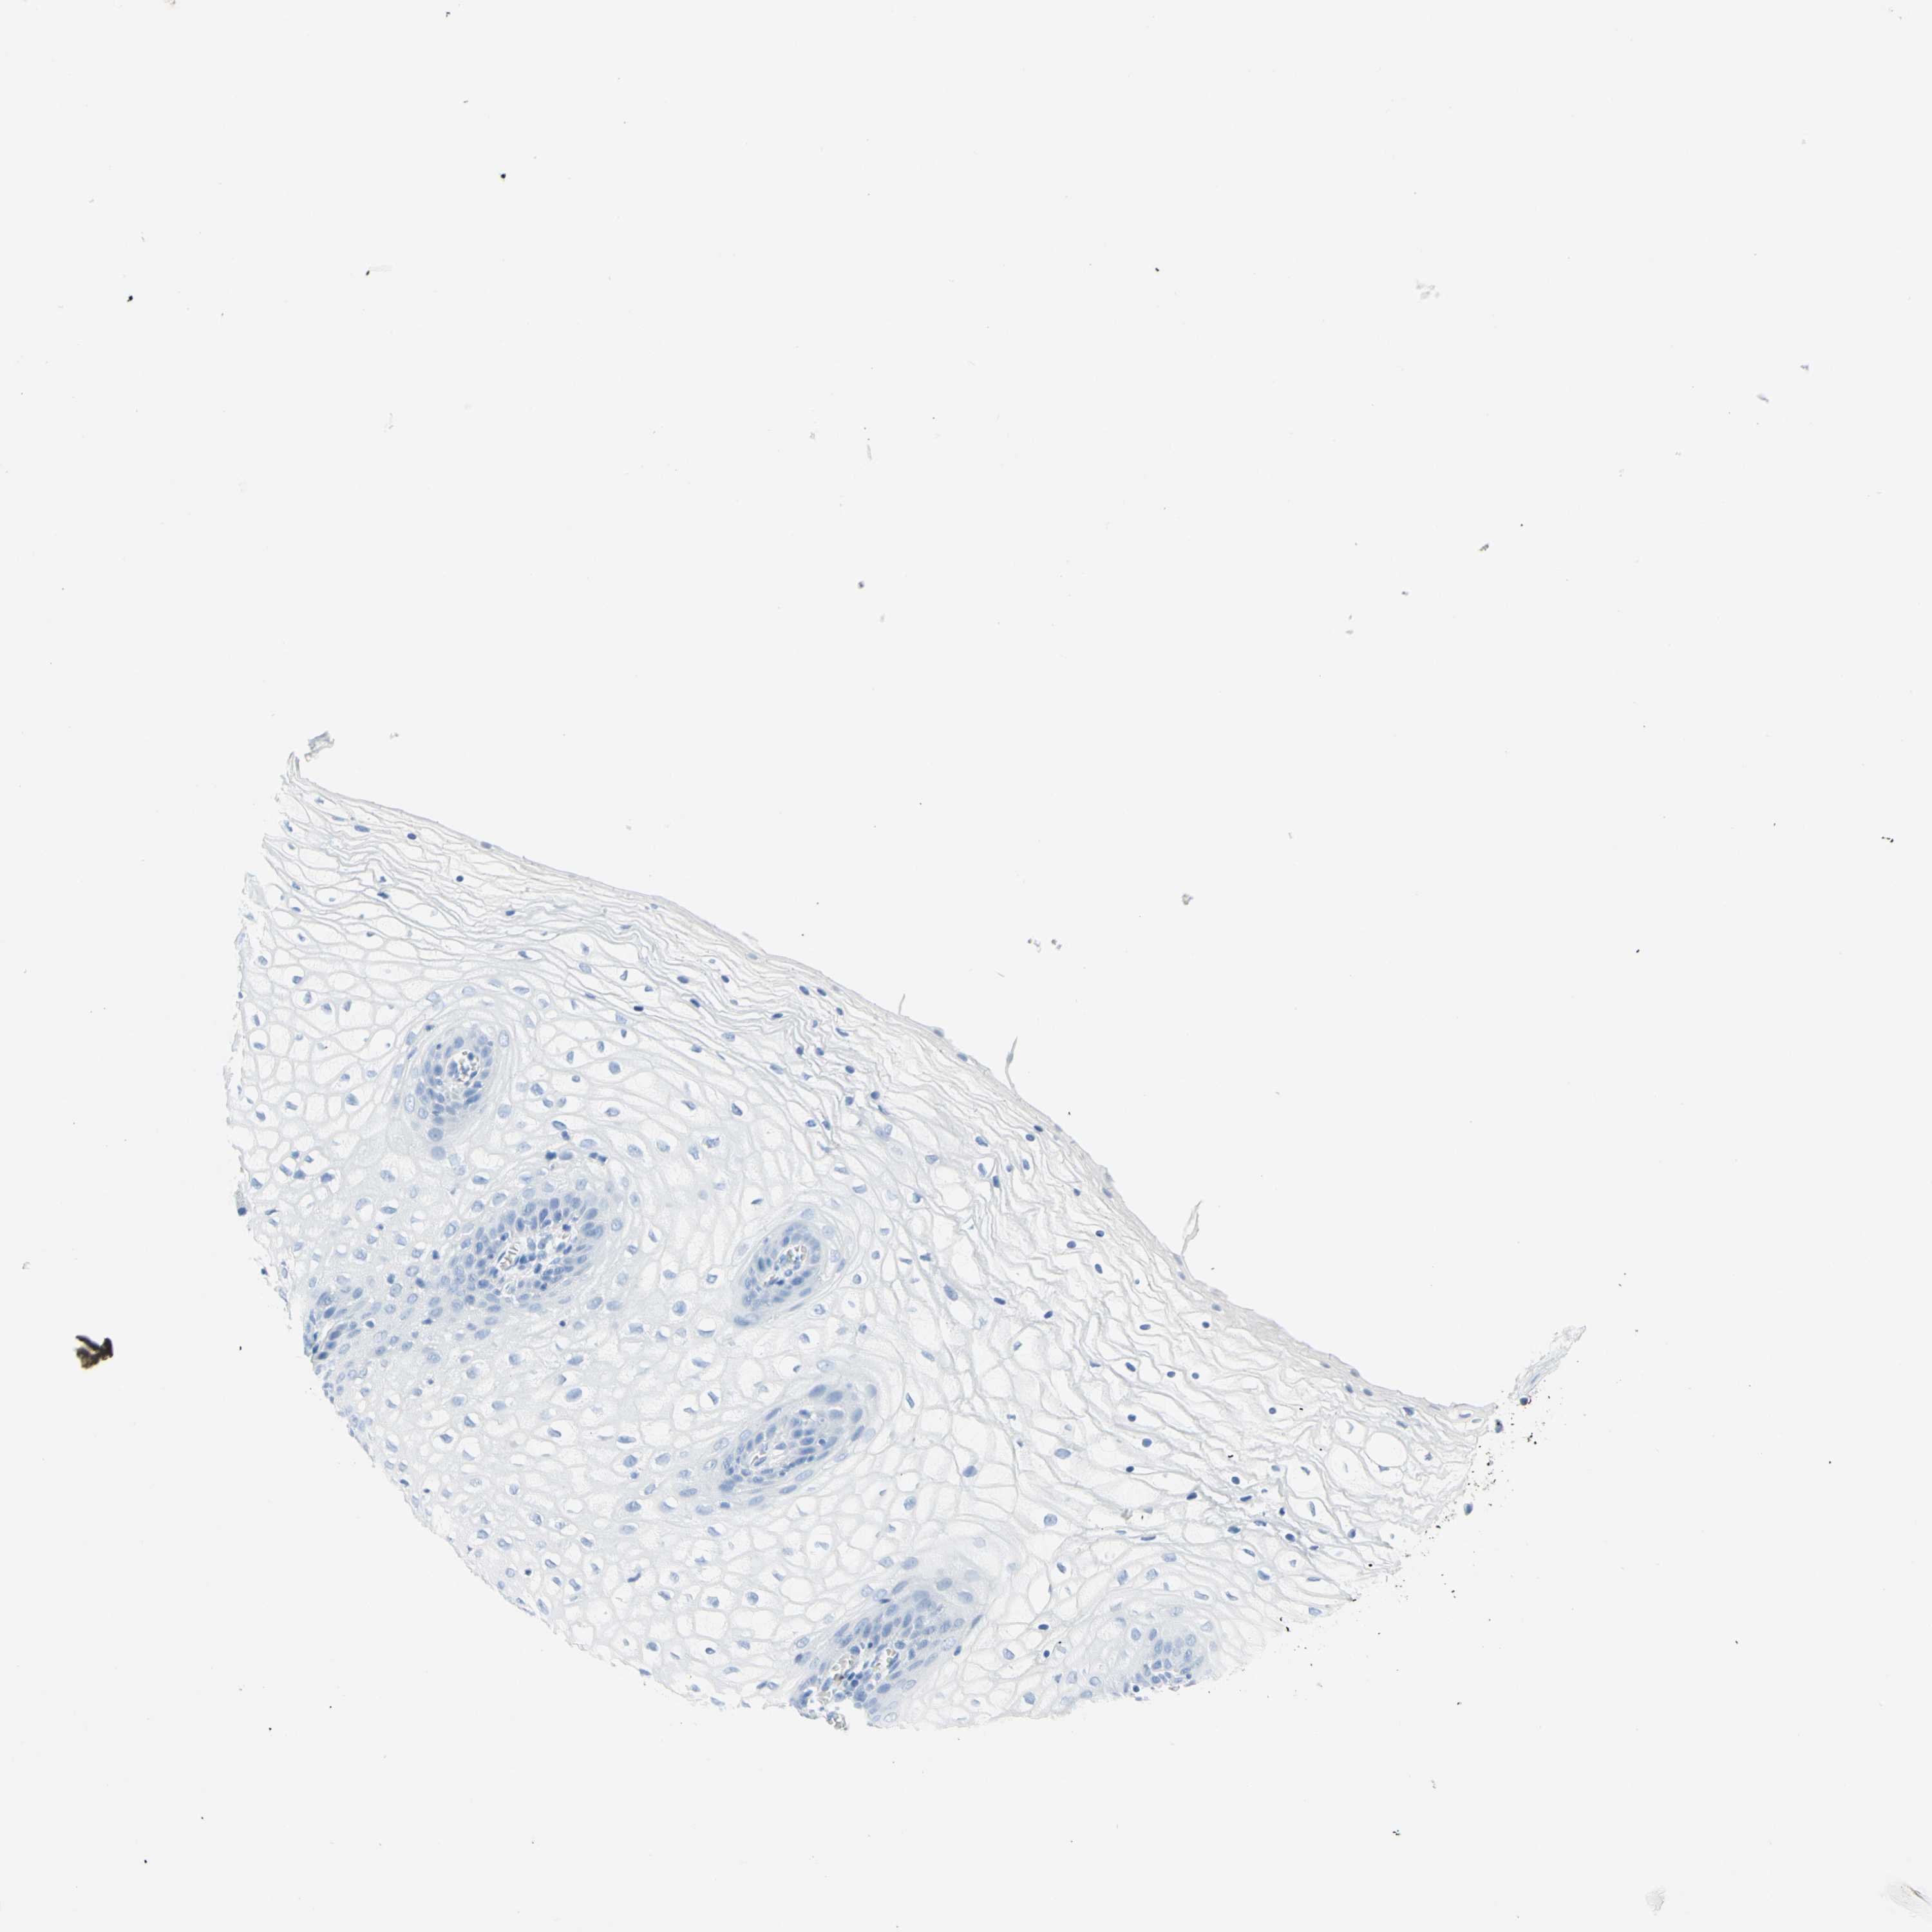

VAGINA - Antibody stainingi

Antibody staining in the annotated cell types in the current human tissue is reported as not detected, low, medium, or high, based on conventional immunohistochemistry profiling in selected tissues. This score is based on the combination of the staining intensity and fraction of stained cells.

Each image is clickable and will lead to virtual microscopy that enables deeper exploration of all samples and also displays staining intensity scores, fraction scores and subcellular localization as well as patient and tissue information for each sample.

Antibody HPA010558Antibody CAB025784

Squamous epithelial cells Not detectedLow